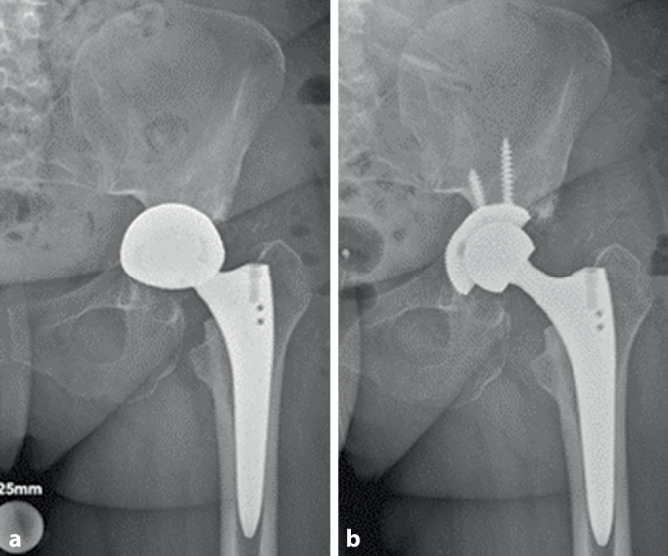

Background: Periprosthetic acetabular fractures primarily pose a problem with cementless implantation techniques and occur in approximately 3.6% of primary and up to 20.9% of revision cases. When a fracture situation exists that affects the integrity of the pelvic columns, stabilization using plate osteosynthesis is necessary, in addition to the implantation of a revision cup. Periprosthetic femoral fractures also primarily occur with cementless techniques and account for 0.4-6.8% of revisions after primary total hip arthroplasty. In addition to the cementless technique, the most common risk factors for the development of PFF are a minimally invasive, ventral approach, female gender, poor bone quality, age > 75 years, and revision surgery.

Treatment: Depending on the degree of risk to the stability of the implant, conservative or surgical treatment can be carried out using osteosynthesis, stem replacement or a combination of both procedures.